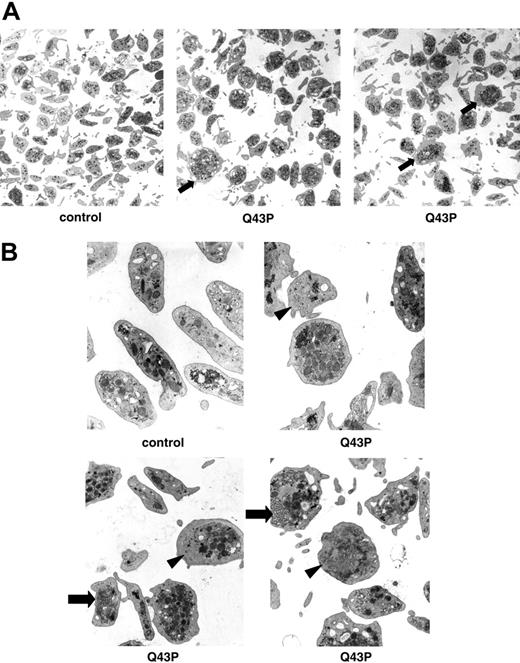

The effect of the Q43P β1-tubulin mutation on platelet morphology

All Q43P β1-tubulin carriers had a normal platelet count, but electron microscopy performed on platelets of 3 Q43P carrier platelets showed the presence of enlarged and rounder platelets compared with the discoid shape of platelets from control subjects (Figure 2A-B), as was also seen in β1-tubulin-deficient mice.7 These abnormal round platelets (about 50% of all platelets) have a disturbed marginal band of microtubules and present with organelle-free zones, centralized platelet granules, and sometimes abnormal membrane complexes.

Ultrastructural analysis of platelets. (A) Electron microscopy of platelets (original magnification, × 7800) of a healthy individual and 2 heterozygous β1-tubulin Q43P carriers (carriers 1 and 2). Almost 50% of Q43P carrier platelets are enlarged and round (arrow). (B) Electron microscopy of platelets (original magnification, × 22 500) of a healthy individual and 3 heterozygous β1-tubulin Q43P carriers, showing cytoplasmic inclusions composed of smooth endoplasmic reticulum and abnormal membrane complexes (arrow). Note also the organelle-free zones in some platelets (arrowhead). There is a normal number of more centralized platelet alpha and dense granules.

Platelet-rich fractions were available from all macrothrombocytopenia patients, 3 unrelated Q43P β1-tubulin carriers from a healthy population (carriers 1, 2, and 4) and from 3 healthy noncarrier controls. Platelet-rich plasma (PRP) was prepared by centrifugation (15 minutes at 150g) of whole blood anticoagulated with 3.8% (wt/vol) trisodium citrate (9:1). The platelet-rich fractions were immediately fixed in 2.5% glutaraldehyde, 0.1 M phosphate buffer at 4°C overnight. After 1 hour postfixing in 1% osmium tetroxide, 0.1 M phosphate buffer at 4°C, the samples were dehydrated in graded series of alcohol and embedded in epoxy resin. Ultrathin sections were cut, stained with uranyl acetate-lead citrate, and examined using a Zeiss electron microscope (Heidelberg, Germany).11